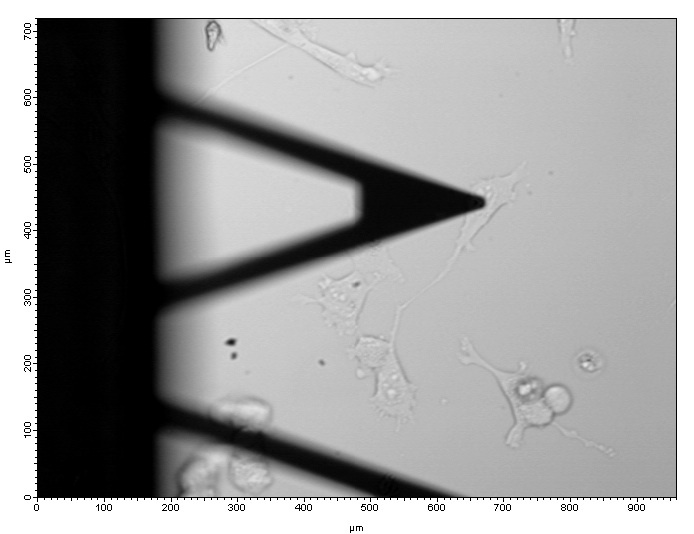

A triangular cantilever is positioned just over a metastatic ovarian cancer cell while preparing to indent and measure the stiffness.